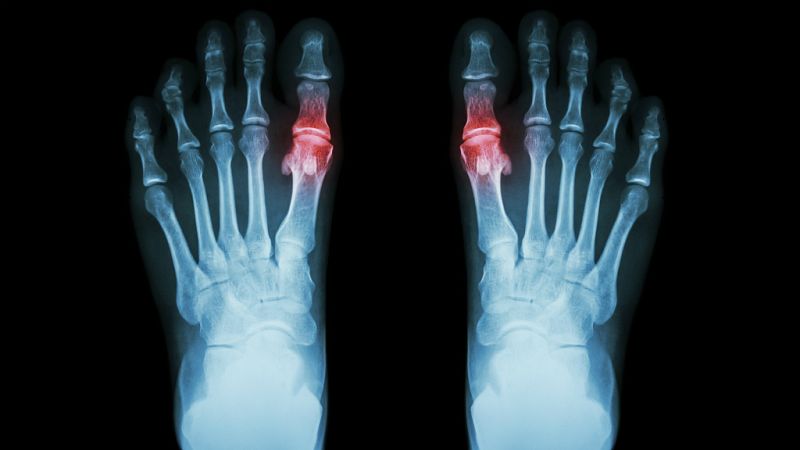

La gota es causada por la acumulación de cristales de ácido úrico en las articulaciones provocando un dolor muy agudo e hinchazón. Generalmente aparecen en forma de ataques que tienen duración de una o dos semanas, para posteriormente desaparecer. Sin embargo, si no se trata correctamente puede cronificarse llegando a formar tofos ¿Qué son? “Una especie de bultos de ácido úrico que hay en las articulaciones”, afirma Aitor Sánchez colaborador de El gallo que no cesa.